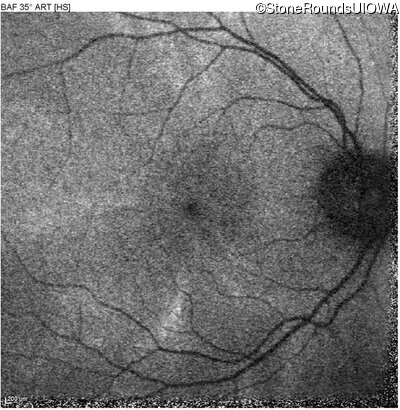

Blue Autofluorescence - Left - 20/20 -1

Exemplar